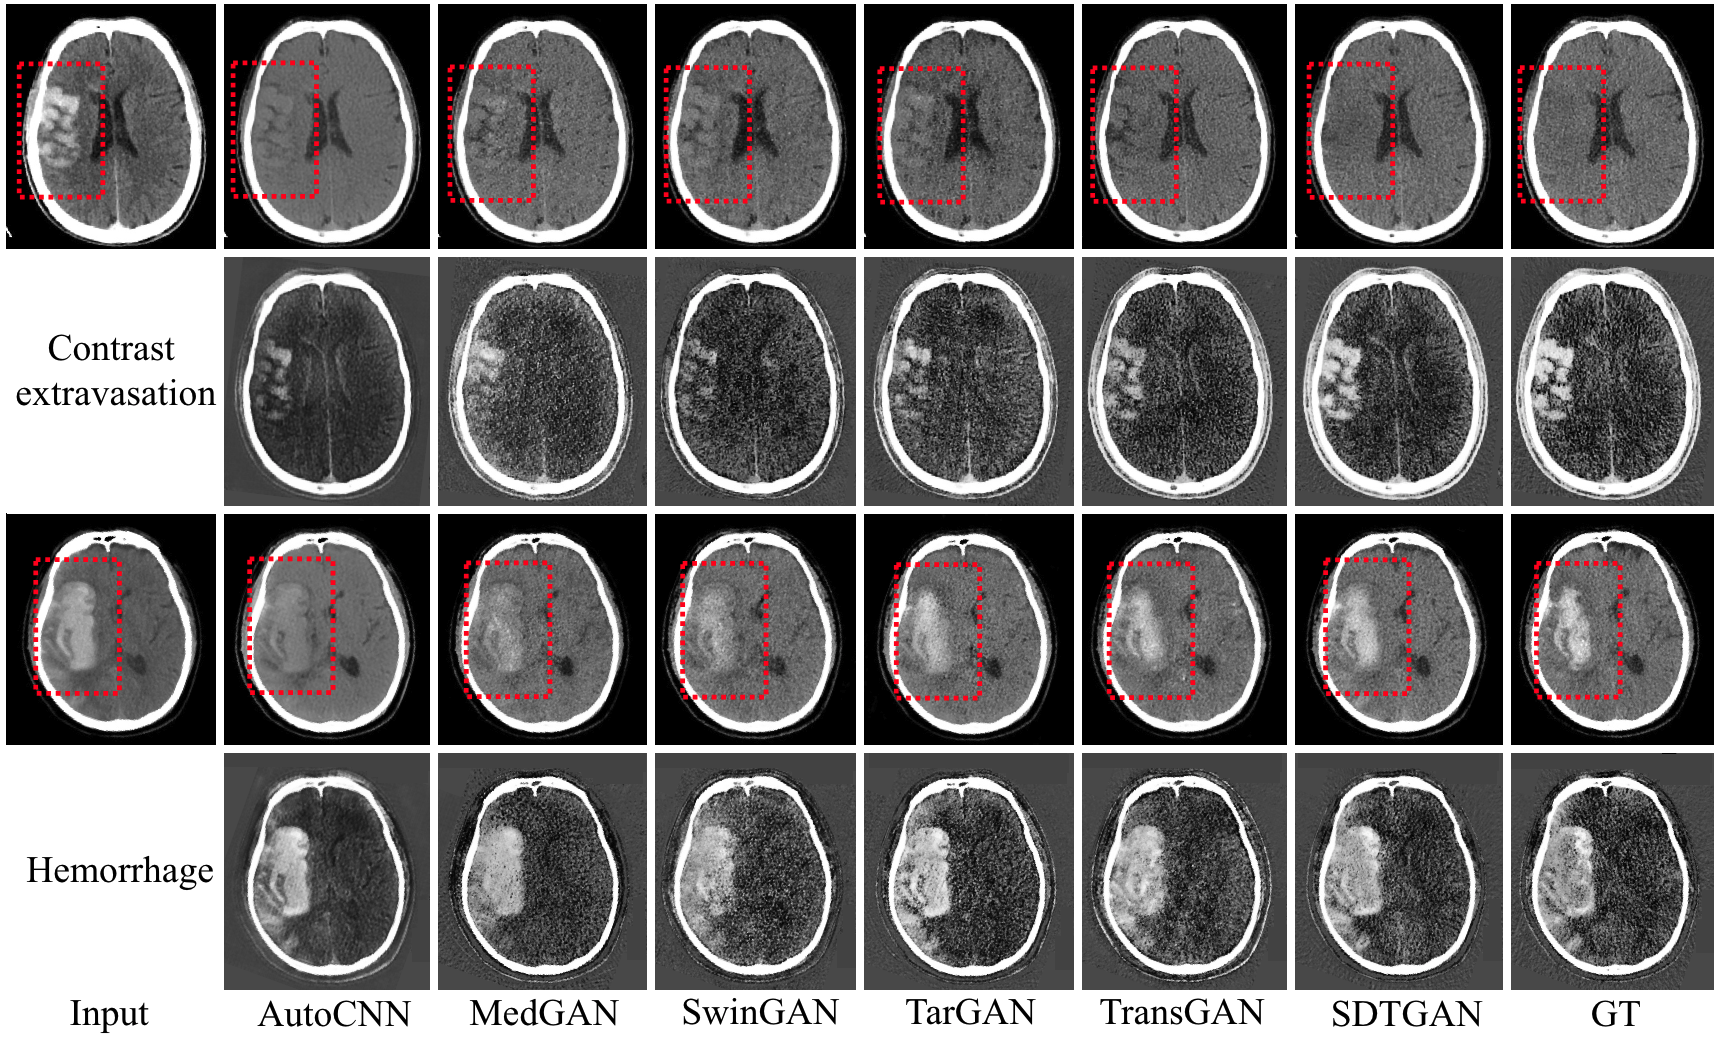

6、探索血栓切除手术后的脑出血诊断新方法

血栓切除术后脑出血的实时诊断对于后续治疗至关重要,但在标准单能量CT(SECT)中难以实现。双能量CT(DECT)扫描仪采用两种不同的能谱,能基于能量相关的衰减特性实时区分出血和造影剂渗漏。由于高昂成本,DECT扫描仪在医院中普及率远不如SECT扫描仪。为了解决这一困境,本研究从SECT图像生成伪DECT图像以实现出血的实时诊断,这是一种基于3D Transformer的多任务学习框架。实验使用DECT数据中的混合120kV图像来近似真实的SECT图像,以解决无法获得真实配对的DECT和SECT的数据问题。结果表明,SDTGAN生成的DECT图像优于当前最先进的方法。

图2 两个典型案例的 DECT 样本的视觉比较。

相关研究成果以“Real-time diagnosis of intracerebral hemorrhage by generating dual-energy CT from single-energy CT”为题发表于Medical Image Analysis。九游体育(www.jiuyou.com)官方网站沈定刚课题组博士研究生江才文为第一作者,九游体育(www.jiuyou.com)官方网站常任正教授沈定刚为通讯作者, 九游体育(www.jiuyou.com)官方网站为第一完成单位、上海临床研究中心为合作单位。